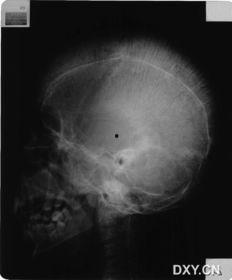

5. 神经系统症状:贫血症还可能影响神经系统,导致注意力不集中、记忆力减退等症状。